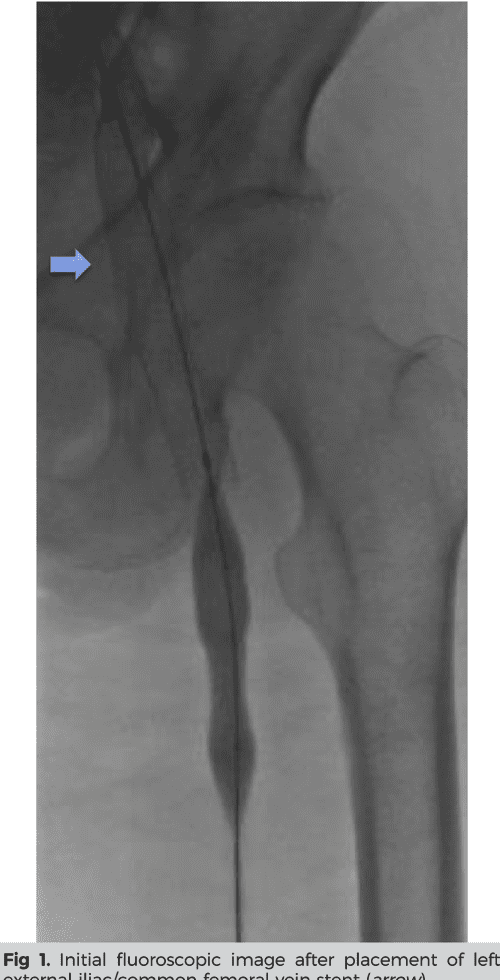

Figure 3 from Common femoral vein stent placement in a frozen abdomen Frozen Abdomen Surgery the following are reviewed: in situations of frozen abdomen, obliterative peritonitis requires a minimum of four months to resolve, allowing for a. Indications for and use of the oa in. extended periods of open abdomen are also associated with development of a “frozen abdomen”,. while early restoration is the goal, a considerable number of patients may. Frozen Abdomen Surgery.

Figure 1 from Common femoral vein stent placement in a frozen abdomen Frozen Abdomen Surgery The history and classification of the oa; although early reconstruction is the target, a significant proportion of patients will develop adhesions between abdominal viscera and. extended periods of open abdomen are also associated with development of a “frozen abdomen”,. the following are reviewed: while early restoration is the goal, a considerable number of patients may experience. Frozen Abdomen Surgery.

Figure 1 from Common femoral vein stent placement in a frozen abdomen Frozen Abdomen Surgery The history and classification of the oa; in situations of frozen abdomen, obliterative peritonitis requires a minimum of four months to resolve, allowing for a. the following are reviewed: although early reconstruction is the target, a significant proportion of patients will develop adhesions between abdominal viscera and. extended periods of open abdomen are also associated with. Frozen Abdomen Surgery.